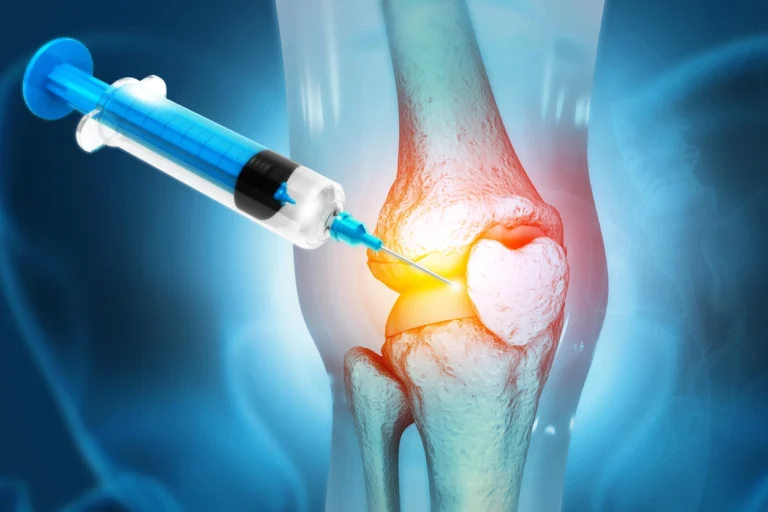

What are Joint Injections?

Joint injections involve delivering medications directly into a joint to relieve pain and inflammation.

These injections are commonly performed in:

Shoulder

Knee

Wrist

Elbow

The procedure is typically guided by ultrasound or fluoroscopy, ensuring precise placement of medication.

Conditions Treated

Arthritis

Joint inflammation

Tendinitis

Sports injuries

Chronic joint pain

Benefits

- Targeted pain relief

- Minimally invasive procedure

- Quick treatment time

- Improved joint mobility